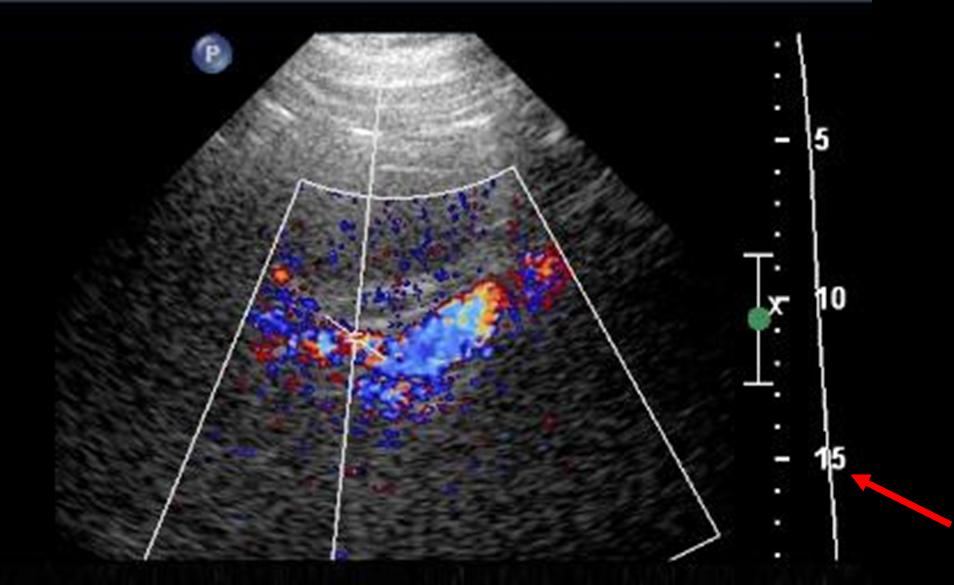

Distal renal artery ultrasound

There is partial visualization of the renal artery